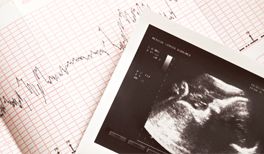

Bildquelle: iStock.com/liseykina

Es gibt spezielle vorgeburtliche Untersuchungen, die man in der Schwangerschaftsvorsorge unter dem Begriff Pränataldiagnostik zusammenfasst. So können schon vor der Geburt chromosomale Erkrankungen wie das Down-Syndrom, Fehlbildungen oder Erbkrankheiten wie Mukoviszidose erkannt werden. ©iStock.com/liseykina